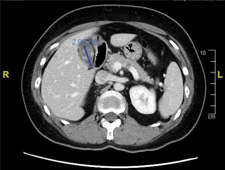

Figure

legends:

A.CT scan showing a 3-cm gallstone

filling the gallbladder.

The CT scan showed a 3-centimeter gallstone that completely filled the gallbladder.